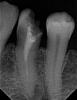

GENRY Опубликовано 25 ноября, 2010 Поделиться Опубликовано 25 ноября, 2010 (изменено) Здравствуйте. Надо перелечить 34 зуб под культевую вкладку+МК.Зуб пломбирован резорцин-формалиновой пастой (~10 лет назад). Буду благодарен за рекомендации по лечению, не связанному с удалением зуба. Вопросы примерно такие:1. Какой порядок и инструменты (методики) распломбирования канала показаны в моем случае? Прочел, что есть специальные жидкости, насколько это реально? Не получится, что и старую пломбу испортишь и новую поставить нельзя будет? 2. Если канал полностью не пройдется, то целесообразно ли ставить ВКВ в этом случае? В одной клинике эндодонт предлагает в этом случае рассверлить канал на глубину достаточную для вкладки, провести 2-3 сеанса депофореза и к ортопеду. Достаточно ли это для жизнеспособности ВКВ? 3.Какой пломбой закрыть перепломбированный канал, чтобы он не инфицировался по новой до установки МК? ( скажем в течениии месяца) 4. Что не должен делать эндодонт (в смысле рассверловки устья и канала), чтобы не создать проблем ортодонту?Спасибо Свежий снимокСнимок 7 месяцев назад Изменено 25 ноября, 2010 пользователем GENRY Ссылка на комментарий